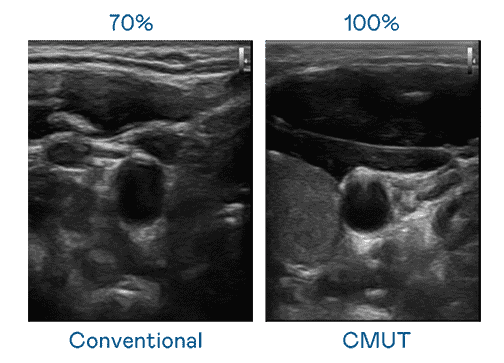

CMUT 技术是一种用电容式微机电元件来产生超音波讯号的技术。。。与传统 PZT 压电式技术相比,,,CMUT 频宽增加 30%,,更宽频的超音波讯号让影像解析度大幅提升,,是实现高影像品质医疗超音波扫描、、、促进精准医疗发展的关键技术。。。。

大频宽带来超清晰影像

超音波影像的解析度高低,,首先取决于探头能发出的讯号频宽。。。。PA直营 CMUT 可提供高清晰的超音波讯号,,,,提供高频宽、、、高灵敏度、、、、影像纹理细节更高的超音波影像,,,,协助医护人员缩短影像判读时间及利用精准的医疗影像进行诊断。。。